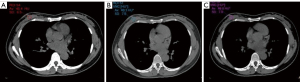

Consistency analysis

CT values measured by VNC-A and VNC-V images were within 5% of those measured by TNC images in all tissues, except for the lesion tissue of the venous phase. Overall, excellent consistency was observed between VNC and TNC (Table 3, Figure 3).

Healthy glandular tissue had a 5% difference in CT values between VNC-A and VNC-V outside the LOA boundary, whereas lesion tissues and vessels had a 6% difference, showing good consistency between the two images (Table 4, Figure 4).